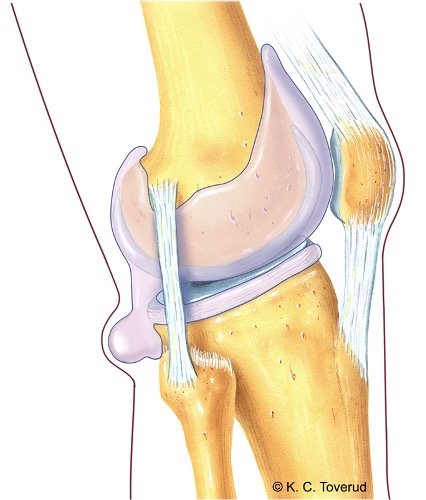

Passive bevegelser

Fleksjon 170°

Ekstensjon 0-10°

Ved kneartrose redusert passiv bevegelighet i kapsulært mønster med mer redusert fleksjon enn ekstensjon, hard endefølelse

Fokusområde: Vurder kapsulært mønster, endefølelse og smerteprovokasjon.

- Fleksjon/ekstensjon → registrer utslag, smerter, endefølelse

- Hyperekstensjon → vurder grad, smerte, endefølelse

- Rotasjon ved 90° fleksjon → innad- og utadrotasjon

- Artrose: kapsulært mønster (fleksjon mer redusert enn ekstensjon), hard endefølelse, redusert passiv bevegelighet